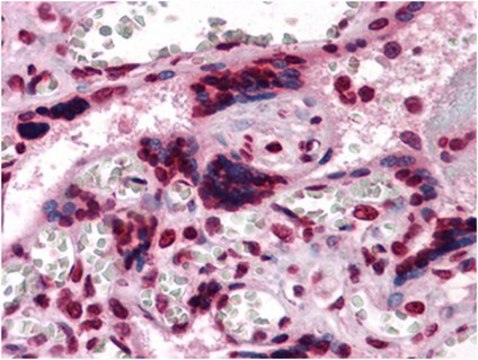

Immunohistochemistry Analysis: A 1:200-1,000 dilution from a representative lot detected CSF1 in human placenta tissue.

Optimal working dilutions must be determined by end user.